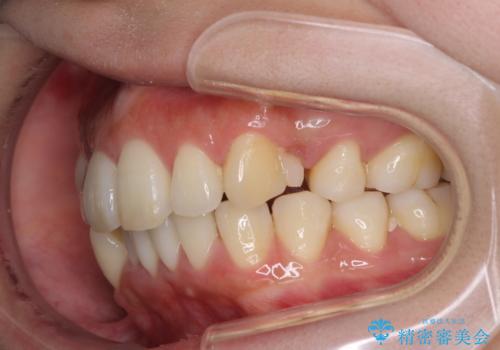

裏側装置で出っ歯の矯正治療

- 出っ歯を目立たない器具で治療したいとのことで来院されました。

上顎の前から4番目の歯を両側抜歯して、上下裏側の装置で前歯を引っ込める計画としました。

裏側からの矯正であったため、表側に比べて少し治療期間を要しました。